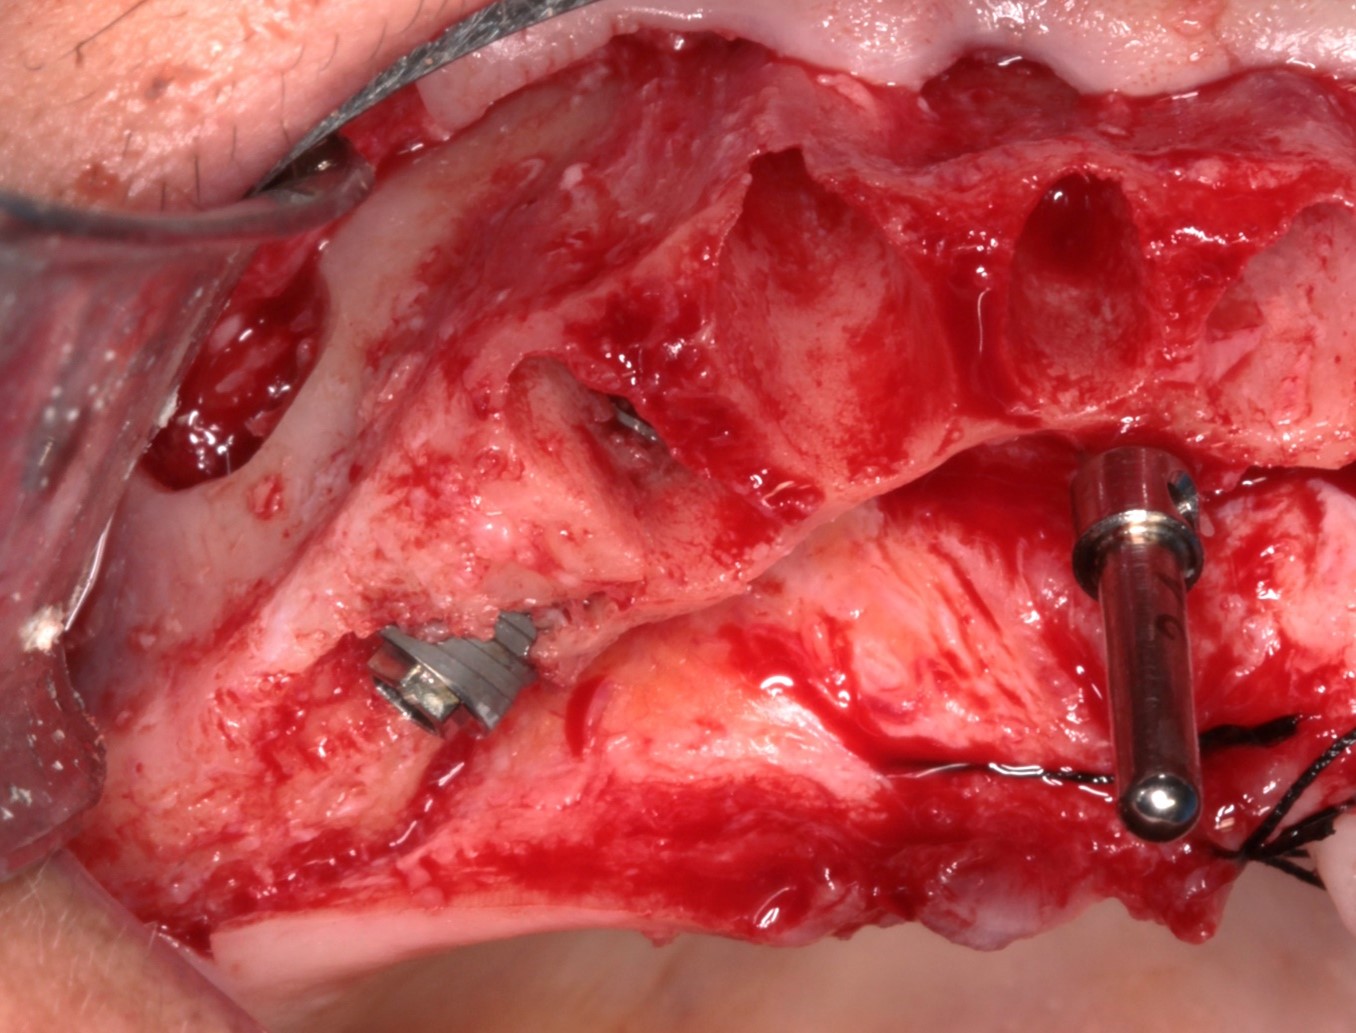

FIG. 06 – Visualização do acesso da janela lateral do seio maxilar e instalação do implante distal de 4.3x15mm realizada.

FIG. 07 – Torque de 80N obtido no implante distal.